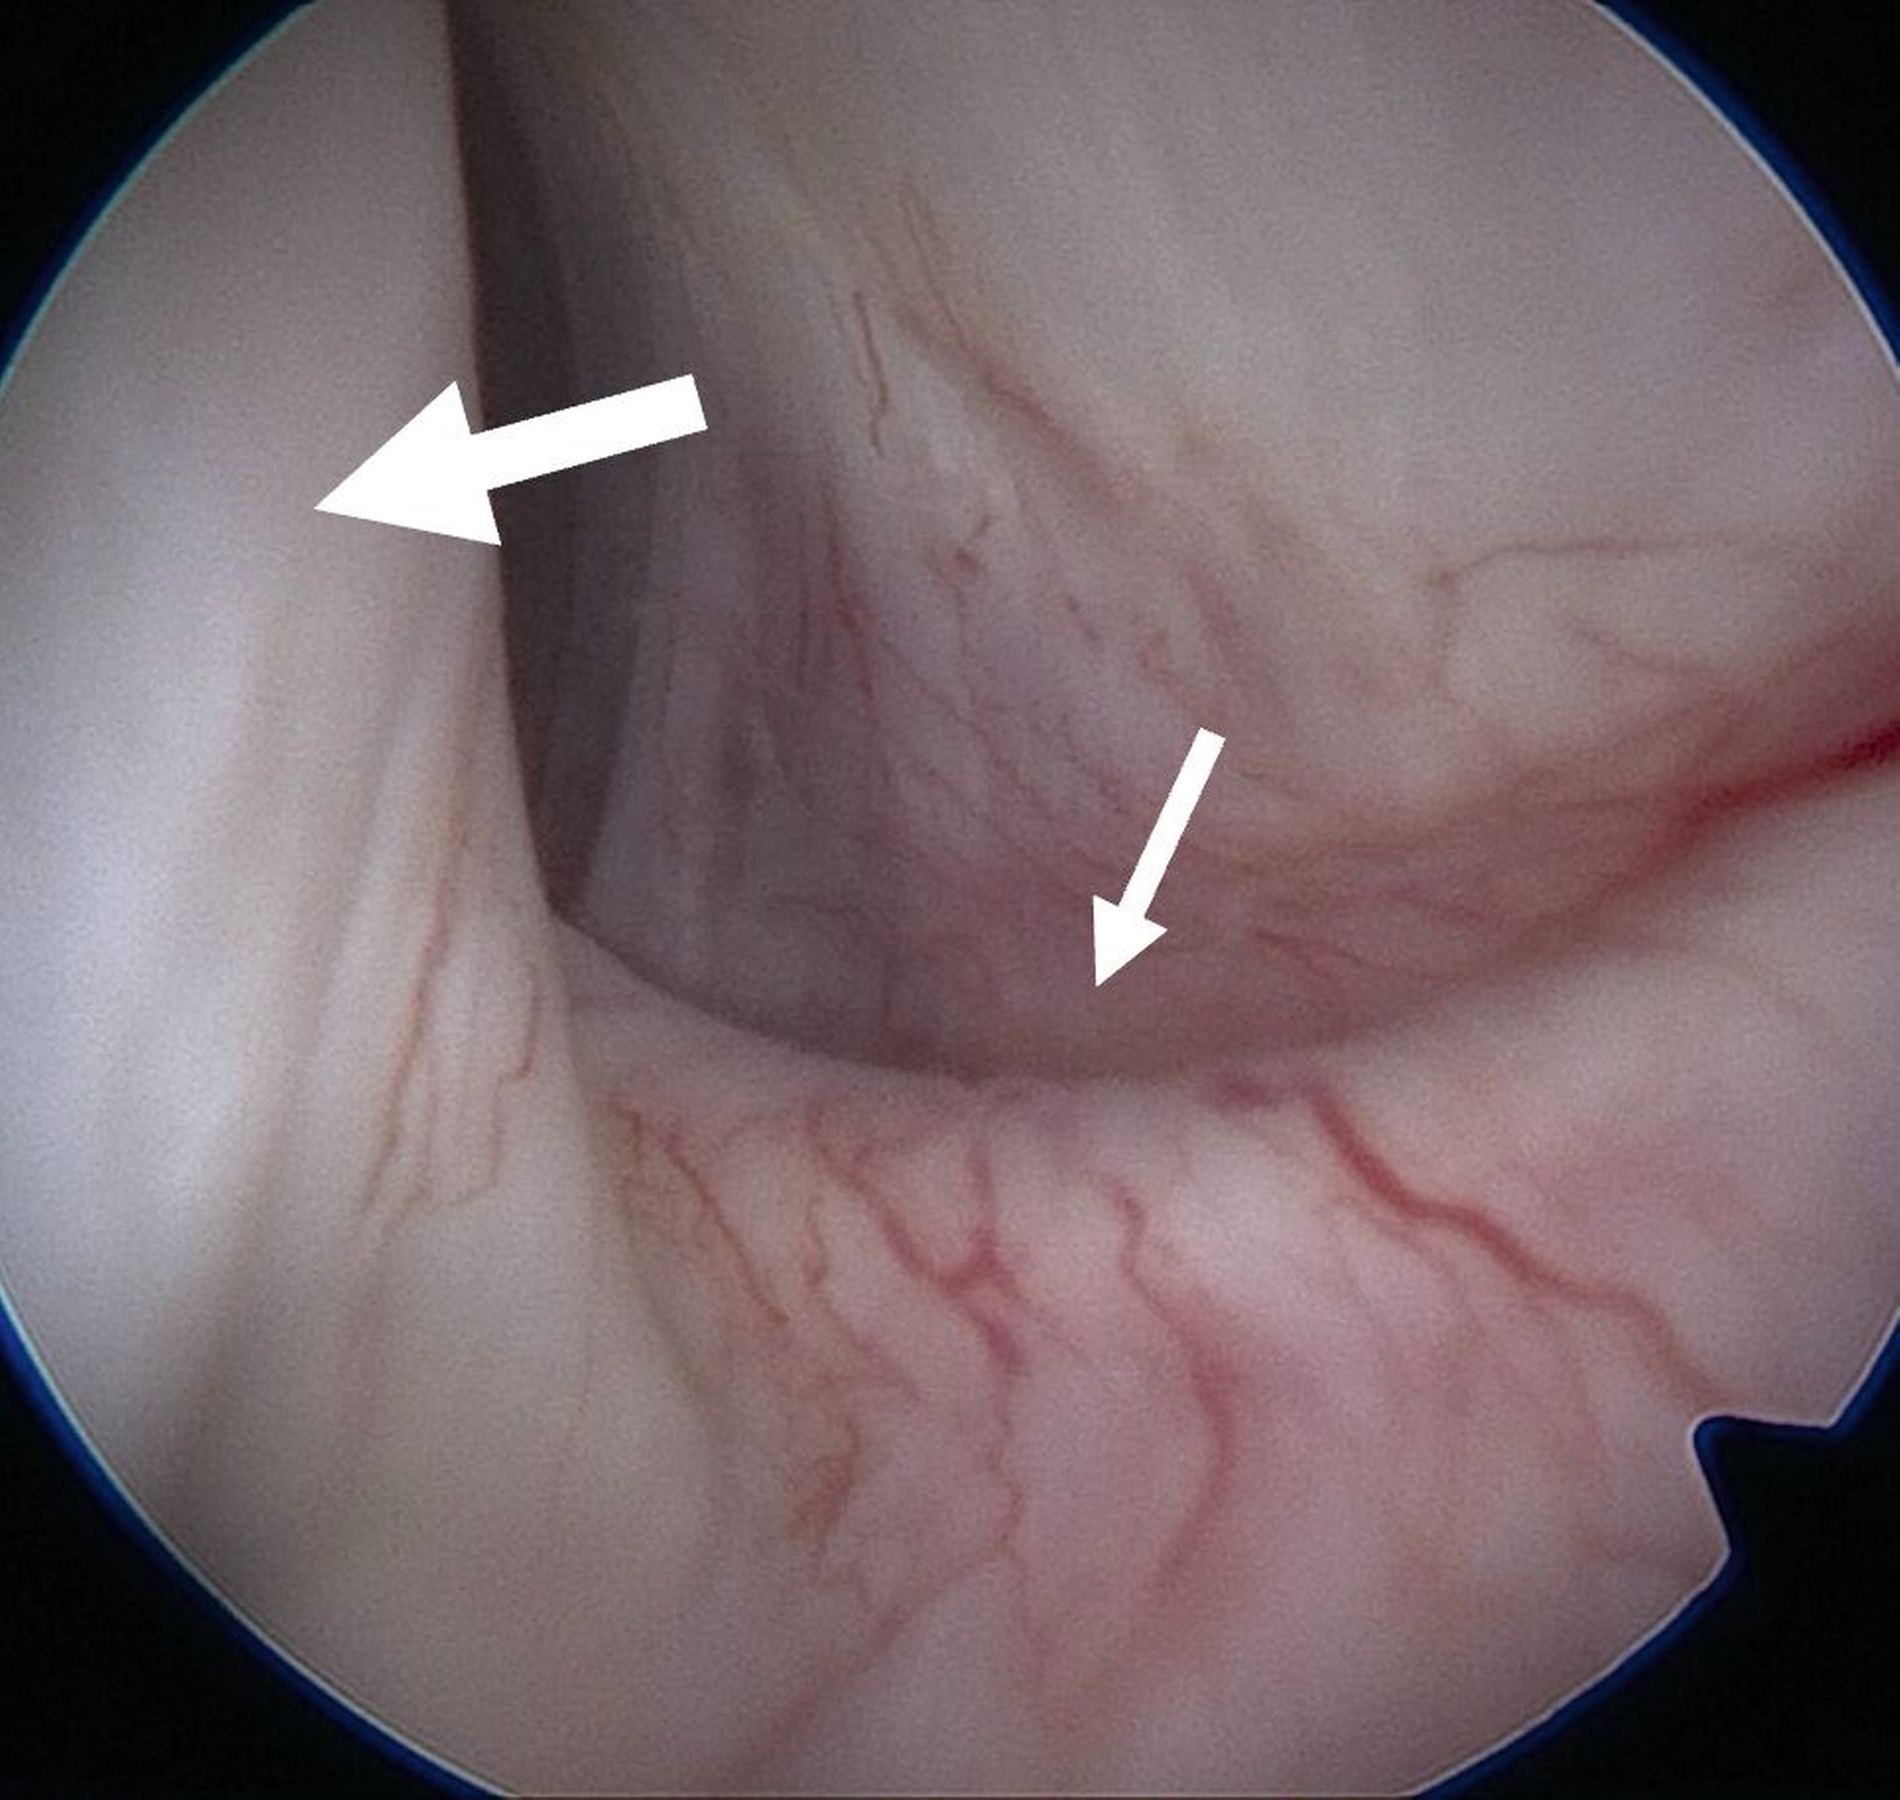

Eine Entzündung im Bereich der Gelenkkapsel (Synovitis) stellt eine häufige Ursache für arthrogen bedingte Beschwerden dar [Mercuri et al., 2025]. Neben der Darstellung des Gelenks und der Behandlung von Pathologien beruht ein positiver Effekt der Arthroskopie auf der Lavage des Gelenks. Dadurch können zum Beispiel proinflammatorische Mediatoren entfernt und intraartikuläre Adhäsionen gelöst werden [Soni, 2019]. Abbildung 2 zeigt die intraoperativen Befunde von zwei Patienten. Es wird jeweils der Übergang zwischen dem hinteren Aufhängungsband und der pars posterior des Discus articularis dargestellt.